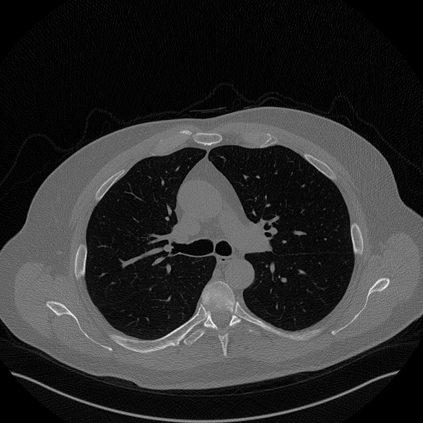

In this work, we present Eformer - Edge enhancement based transformer, a novel architecture that builds an encoder-decoder network using transformer blocks for medical image denoising. Non-overlapping window-based self-attention is used in the transformer block that reduces computational requirements. This work further incorporates learnable Sobel-Feldman operators to enhance edges in the image and propose an effective way to concatenate them in the intermediate layers of our architecture. The experimental analysis is conducted by comparing deterministic learning and residual learning for the task of medical image denoising. To defend the effectiveness of our approach, our model is evaluated on the AAPM-Mayo Clinic Low-Dose CT Grand Challenge Dataset and achieves state-of-the-art performance, $i.e.$, 43.487 PSNR, 0.0067 RMSE, and 0.9861 SSIM. We believe that our work will encourage more research in transformer-based architectures for medical image denoising using residual learning.